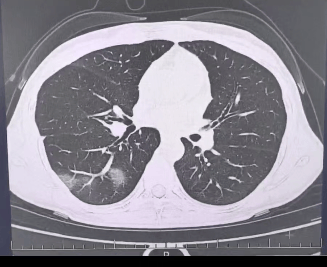

检查结果显示比特币美元,

程女士的好几叶肺

都出现了“白肺”现象比特币美元,

指间血氧饱和度只有 88%比特币美元,

图源:杭州市第三人民医院微信公众号